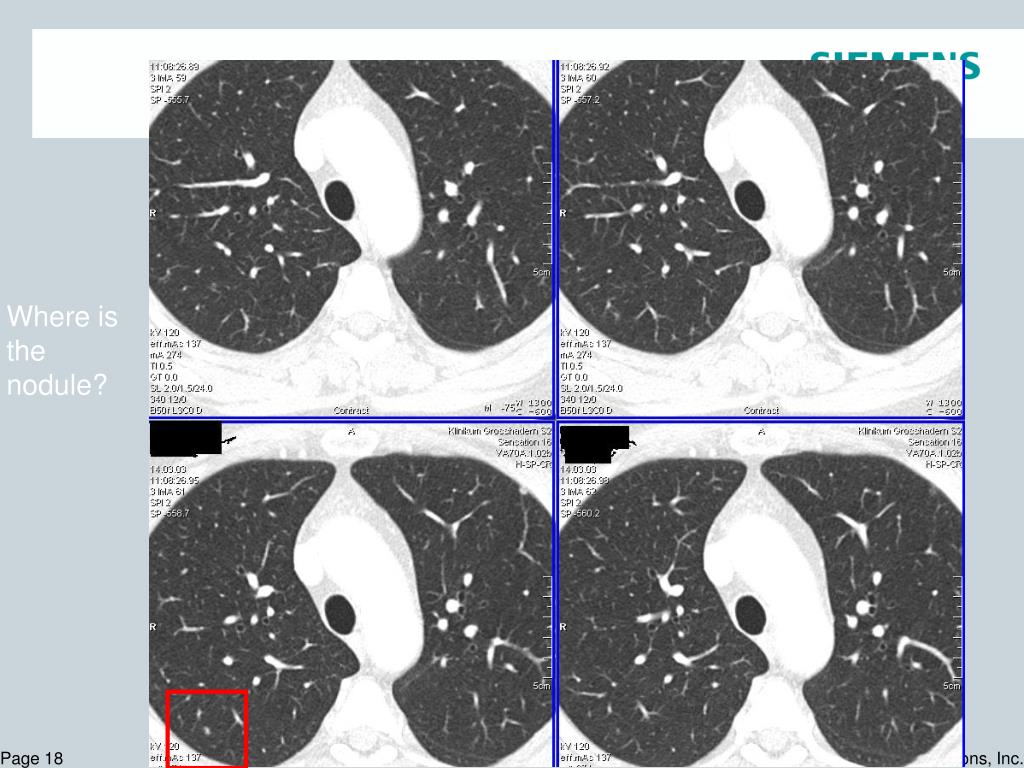

18. Where is the nodule?